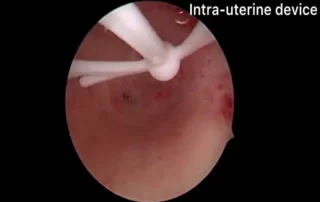

DOI: 10.36205/trocar7.2026005 - Hysteroscopic Resolution of a Failed Pregnancy in the Cornual Region of the Uterus Associated with Uterine Synechiae: Case Report

Luis Pablo Lopez Rivero, Pamela Delgadillo To

Hysteroscopic Resolution of a Failed Pregnancy in the Cornual Region of the Uterus Associated with Uterine Synechiae

DOI10.36205/trocar7.2026006